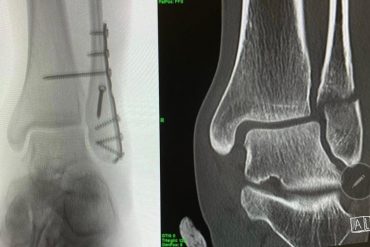

Marcel Hirscher a suferit o accidentare la Red Bull Romaniacs

Marcel Hirscher, austriacul cu un palmares legendar în schiul alpin, s-a accidentat și nu mai poate continua la Red Bull…